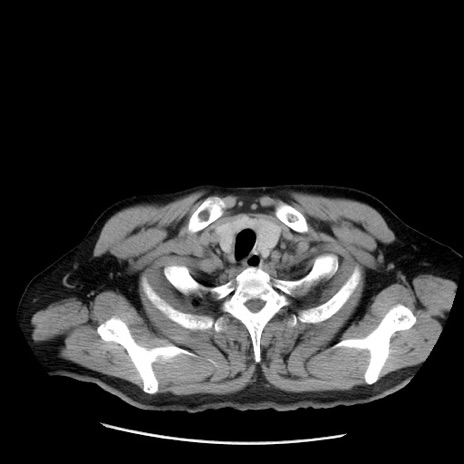

症例20(横断像)

【症例】 60歳代男性

【主訴】 腹部膨満、嘔吐

【現病歴】5日前頃より倦怠感を認め食事量減少し4日前の朝嘔吐、食事摂取困難となった。 3日前近医受診し点滴施行され整腸剤などを処方された。 当日他院を受診し、腹部膨満著明、炎症反応の上昇(CRP10.8、WBC11200)あり、紹介受診となる。

【身体所見】 意識JCS1 受け答えがはっきりしないBP 111/57mHg、 P 67bpm、、BT35.2°C、SpO2 97%(RA)、 腹部:膨隆、打診で鼓音あり、全体的に圧痛有り、腸蠕動音(-)、反跳痛ははっきりせず。

【データ】WBC 11400、CRP 14.20